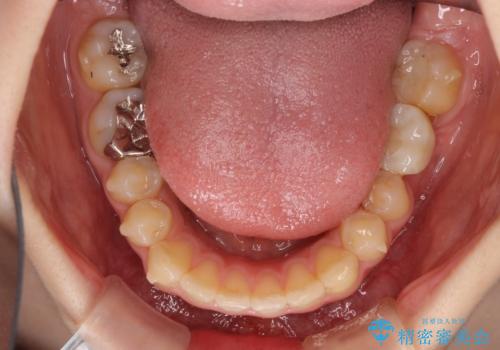

- 口の閉じにくさと割れてしまった奥歯を気にして来院された患者様です。

IPR(歯と歯の間を削る)と歯列全体の後方移動によって口元が引っ込むように設計し、インビザラインにより治療を行うこととしました。

割れてしまった奥歯は抜歯し、矯正治療中の良いタイミングでインプラントを埋入することとしました。

上下正中がずれていたため、抜歯による矯正治療も検討しましたが、口元がそれほど突出していなかったため、非抜歯にて矯正することになりました。

その結果正中のズレは残りましたが、口を閉じたときの感覚や奥歯の咬み合わせには全く問題なく、患者様には大変満足していただきました。